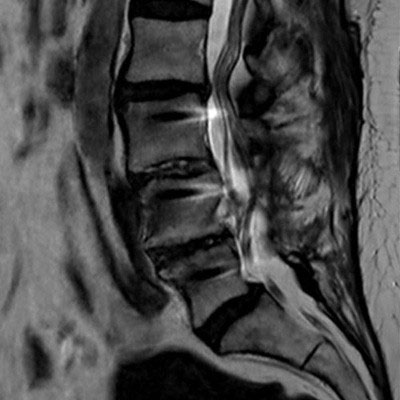

Lumbar Spine with metal implant, routine and fast

Utrecht Medical Center, The Netherlands

**Only for use with MR Safe or MR Conditional Implants by strictly following the Instructions for Use.